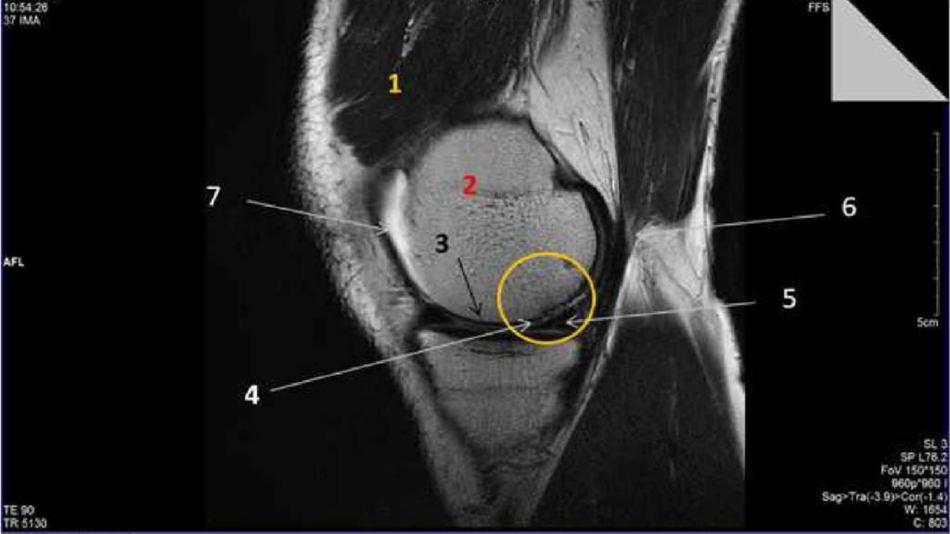

Mini-Magnet-Resonanz Experimente und Meniskus-Schaden in MR-Bildern

FührungGeführte Tour: Forschung am Hochfeld MR ZentrumThema: Gesundheit TechnikWie können wir in den Körper eines Menschen blicken, ohne zum Skalpell zu greifen? Eine Möglichkeit dafür ist die Magnetresonanztomografie (MRT). Mit ihr kann man Anatomie, Stoffwechsel, Verletzungen und Erkrankungen ohne Strahlenbelastung untersuchen. Begleiten Sie uns auf einer Tour durch das Hochfeld MR Zentrum, das über den stärksten MR-Scanner Österreichs mit einer Magnetfeldstärke von 7 Tesla verfügt.Medizinische Forschungsmeile17:00 - 22:30 -